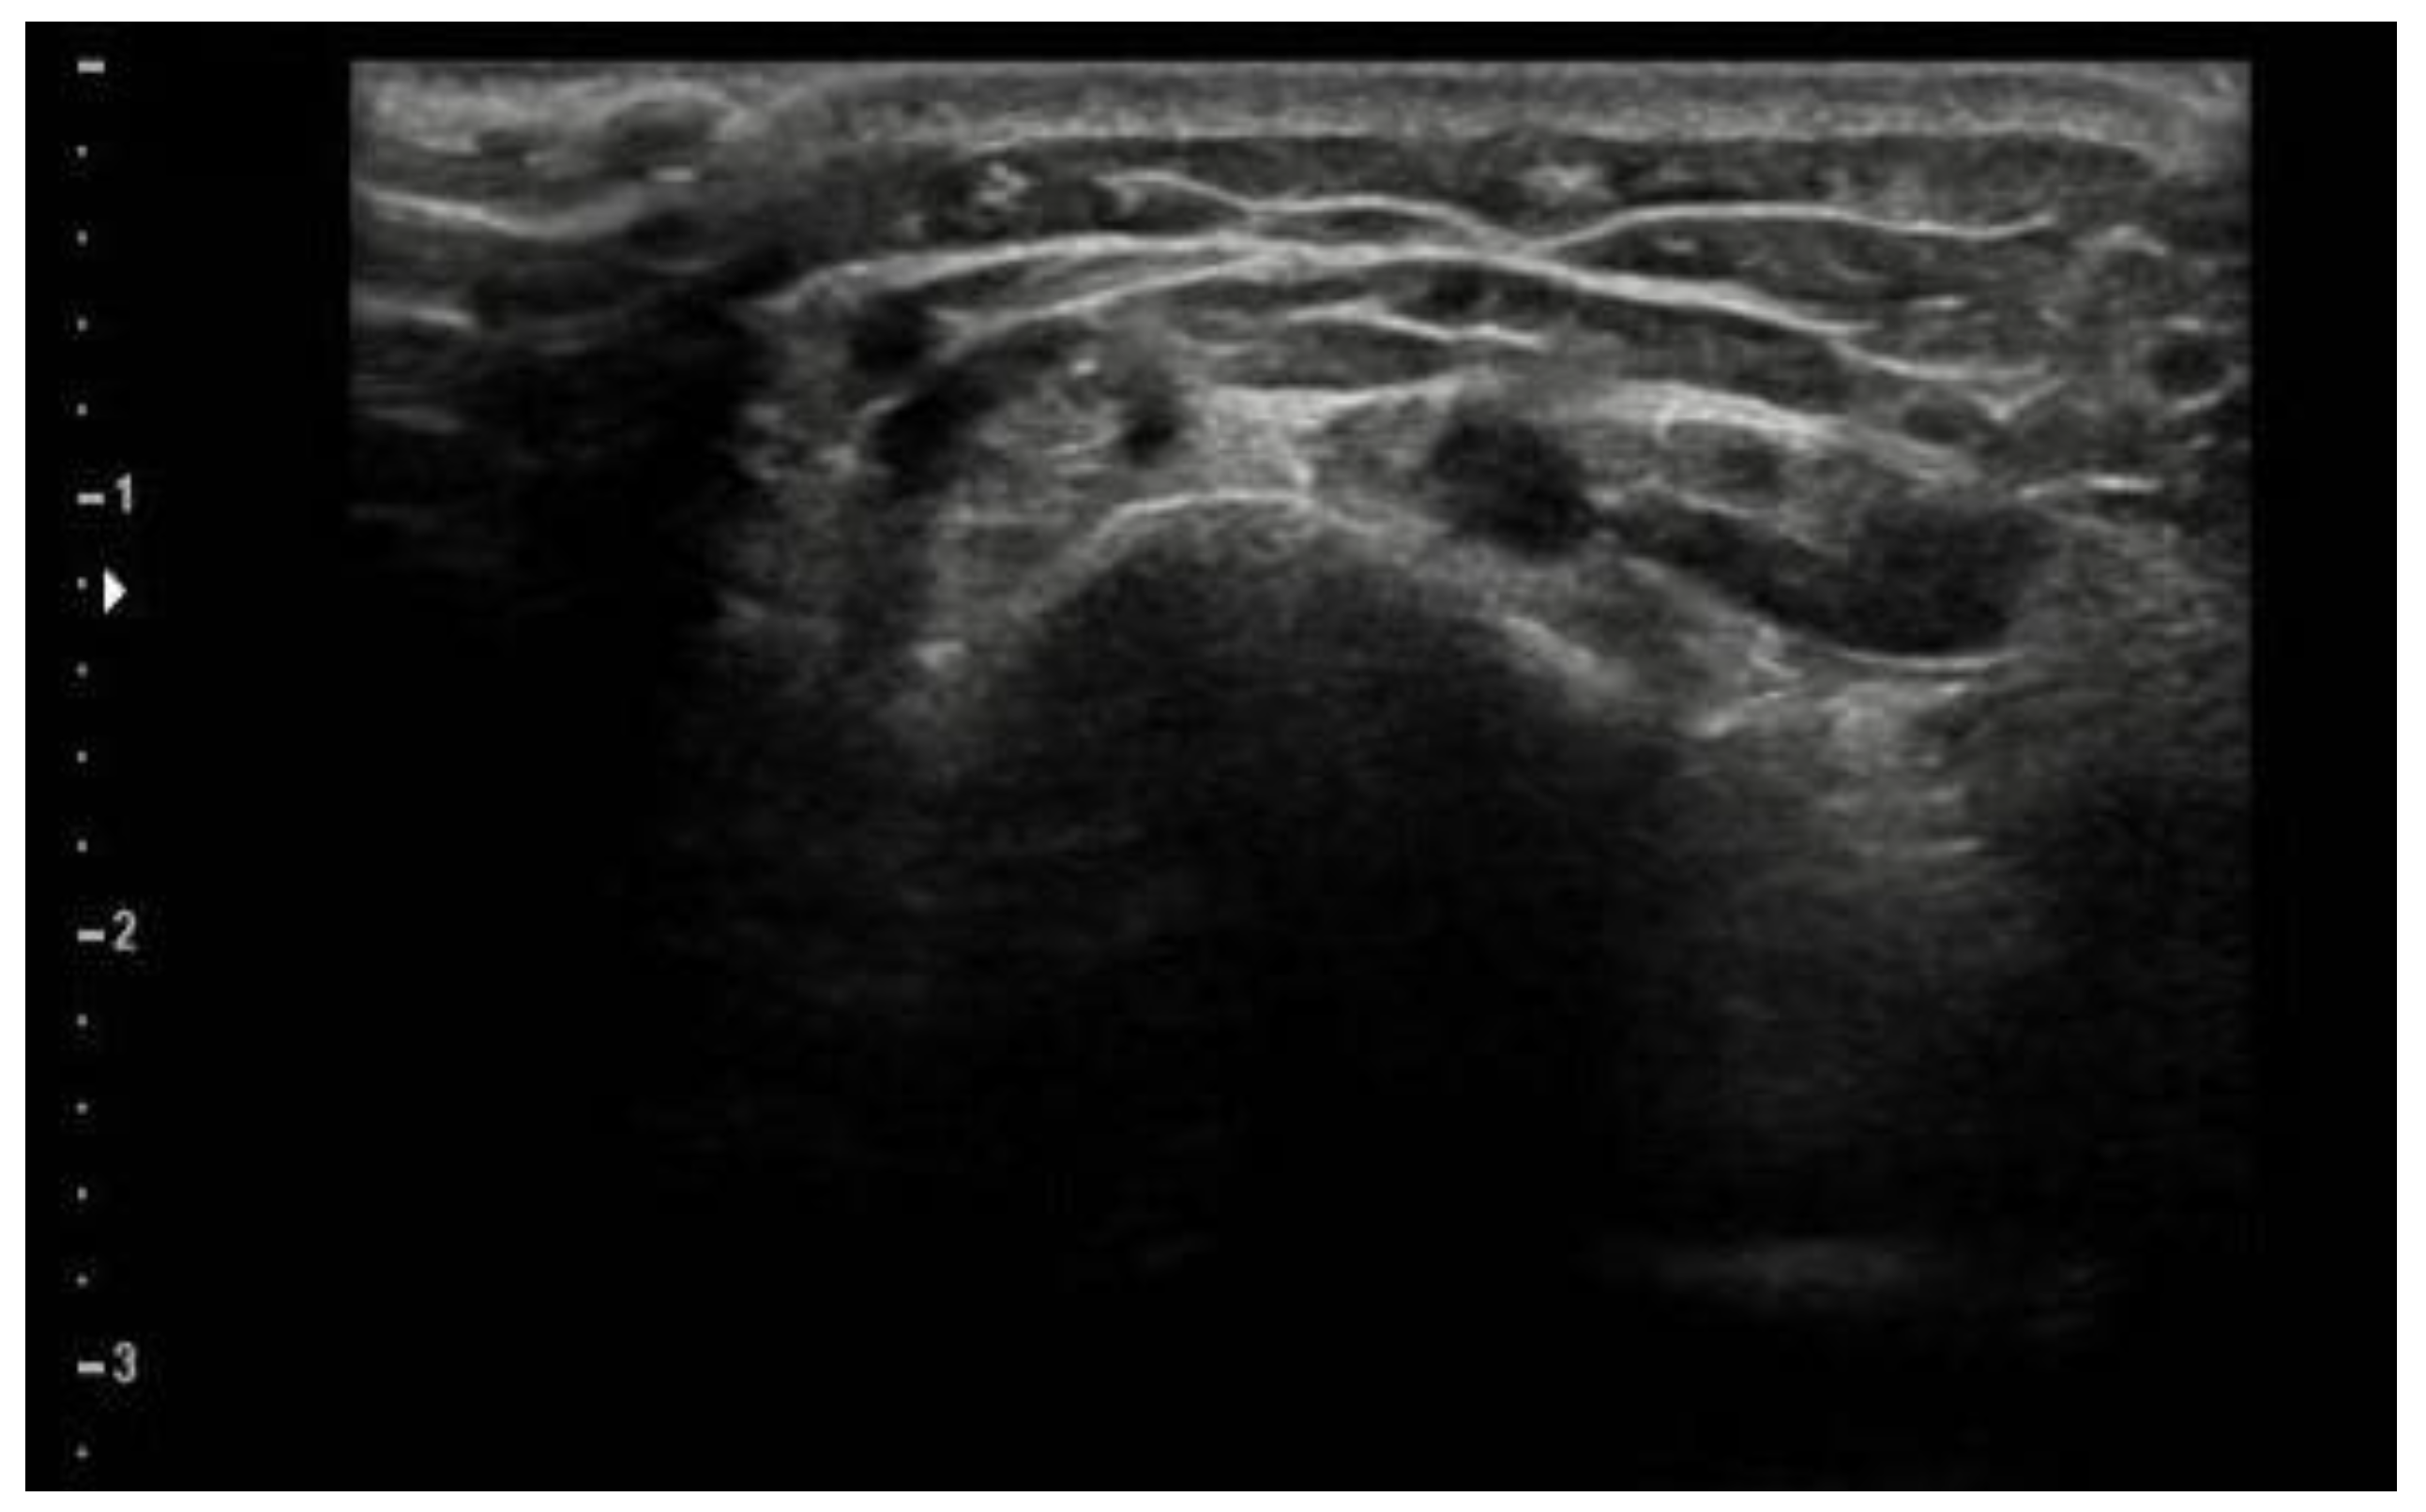

2. Case Presentation

2.1. Evaluation